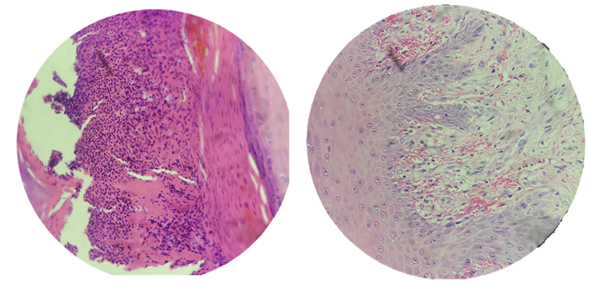

Sections 1 and 2 show skin with representation down to the subcutaneous cellular tissue. At the level of the epidermis, mature keratinized squamous epithelium is visualized, the stratum corneum shows the presence of a crust, with abundant cellular debris, as well as orthokeratosis parakeratosis. The basal layer shows marked spongiosis, with reactive epithelial changes, plus lymphocyte exocytosis. The superficial dermis shows a moderate chronic inflammatory infiltrate, lymphoplasmacytic, superficial perivascular location, with marked extravasation. Microorganisms are not observed.